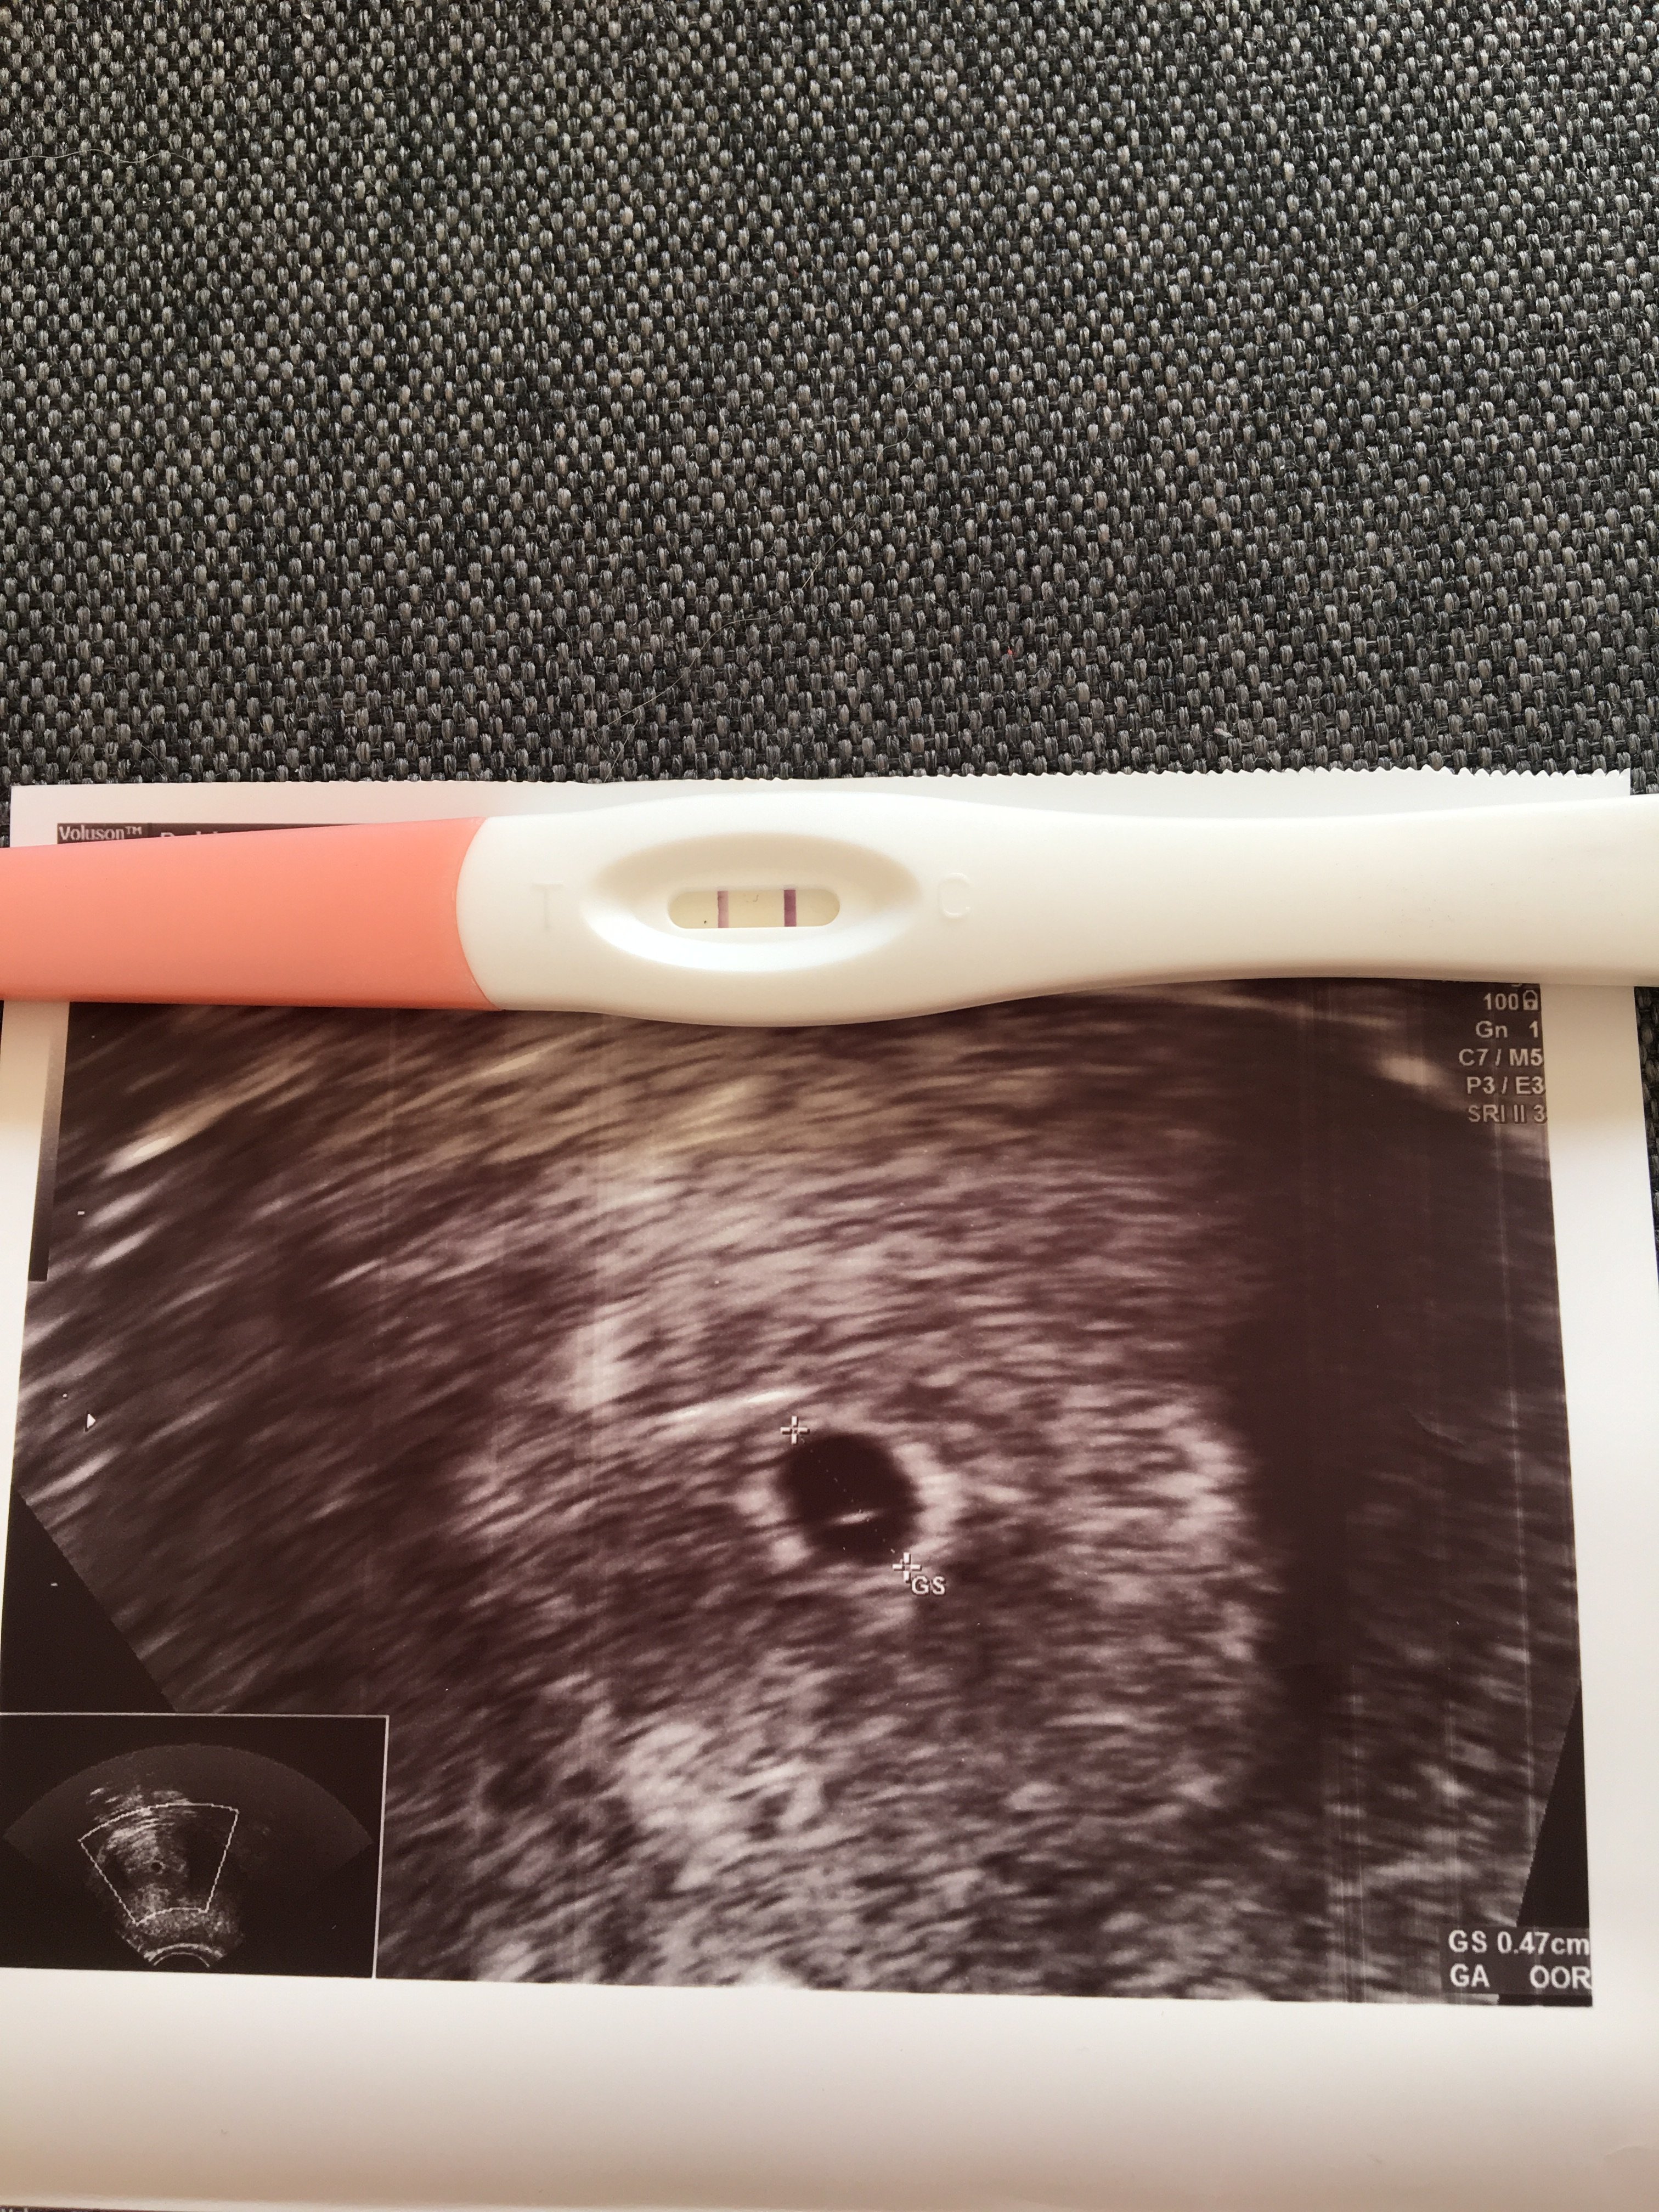

Tak pęcherzyk był 16 dpt ale bardzo się bała bo miałam niska bete. Był miał pół centymetra i z pęcherzykiem żółtkowym jakimś minimalnym ❤❤

Tak mam jeszcze zastrzyki codziennie robię jeden. Biorę tez encorton 10 mg.

Beta 6 dpt 14

8 dpt 30

11 dpt 120

13 dpt 330

15 dpt 680

16 dpt 890 ale pęcherzyk już był ❤️❤️